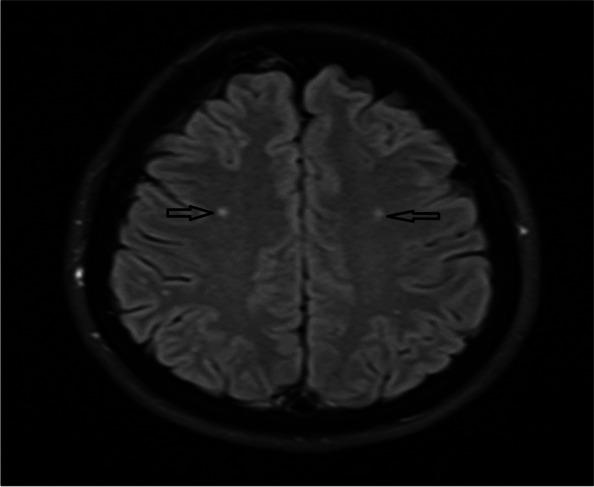

BACKGROUND/AIM: White matter lesions (WML) are more frequently observed in migraine patients than in the average population. Associations between Helicobacter pylori (H. pylori) infection and different extraintestinal pathologies have been identified. Here, we aimed to investigate the association between H. pylori infection and WML in patients diagnosed with episodic migraine.

A retrospective study was conducted with 526 subjects with a diagnosis of episodic migraine. Hyperintensity of WML had been previously evaluated in these patients with brain magnetic resonance imaging (MRI) examinations. Previous endoscopic gastric biopsy histopathological examination of the same patients and reports on H. pylori findings were recorded. The demographic characteristics of the patients, such as age, gender and chronic systemic diseases such as hypertension and diabetes mellitus (DM) were recorded. Statistical evaluation was made.

Evaluation was made among 526 migraine patients who met the inclusion criteria, comprising 397 (75.5%) females and 129 (24.5%) males with a mean age of 45.57 ± 13.46 years (range, 18-69 years). WML was detected on brain MRI in 178 (33.8%) patients who were also positive for H. pylori (p <  0.05). Subjects who are H. pylori-positive with migraine, WML were observed at a 2.5-fold higher incidence on brain MRI (odds ratio: 2.562, 95% CI 1.784-3.680). WML was found to be more significant in patients with hypertension and migraine than those without (p <  0.001). Older age was also found to be associated with WML (OR = 1.07, 95% CI: 0.01-0.04, p <  0.001). The age (p <  0.001), H. pylori (p <  0.001), hypertension (p <  0.001), and hypertension + DM (p <  0.05), had significant associations in predicting WML according to the multivariate logistic regression analysis. The presence of hypertension had a higher odds ratio value than the other variables.

It was concluded that H. pylori infection, as a chronic infection, can be considered a risk factor in developing WML in subjects with migraine.